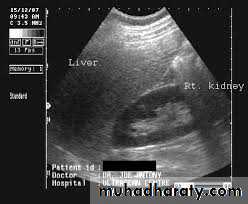

The kidney is bean shaped and has bright central echoes because of the fat surrounding the collecting system.

Normal renal ultrasound.

A longitudinal view of the right kidney was obtained by passing the sound beam through the right lobe of the liver. The kidney is seen behind this, outlined by the markers. The central bright echoes in the kidney are due to fat around the collecting system.